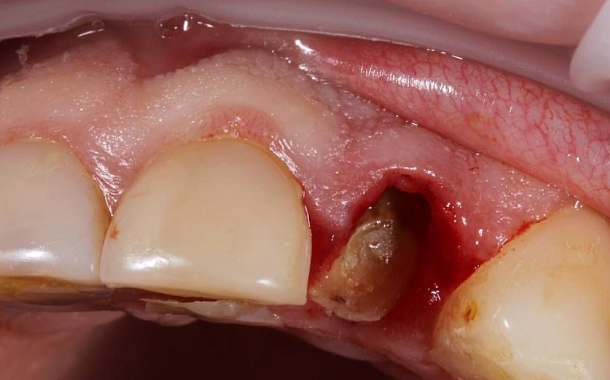

- Удаление зуба было бережным (сохранился объем костной ткани в месте лунки удаленного зуба).

- Обработка лунки и подготовка ложа для имплантата.

- Установка имплантата в запланированном положении, заполнение пространства лунки костно-пластическим материалом, наложение швов.

Хирургические вмешательства всегда неприятны, а немедленная имплантация зубов сводит их до минимума, сокращая сроки лечения до нескольких месяцев. - Сохранение анатомии гребня альвеолярного отростка

Даже после самого бережного и атравматичного удаления зуба и сохранения лунки удаленного зуба, без жевательной нагрузки через 6 месяцев происходит атрофия — уменьшается объем костной ткани гребня альвеолярного отростка, резко сокращается количество кровеносных сосудов, ухудшается плотность и качество костной ткани, что порой затрудняет или может сделать невозможной установку дентального имплантата и требует дополнительных мероприятий по восстановлению утраченной кости.

Одномоментное удаление и установка зубного импланта в лунку помогают сократить до минимума костно-пластические и мягкотканные манипуляции, сохранить анатомию гребня альвеолярного отростка и сформировать естественный профиль прорезывания искусственной коронки, то есть создать иллюзию своего зуба.